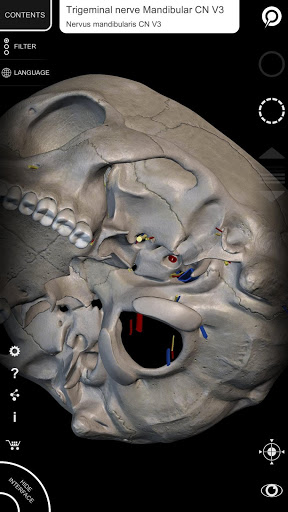

"Anatomía - Atlas 3D" permite estudiar la anatomía humana de forma fácil e interactiva.

A través de una interfaz sencilla e intuitiva es posible observar cada estructura anatómica desde cualquier ángulo.

Los modelos anatómicos 3D son especialmente detallados y con texturas de hasta una resolución de 4k.

La subdivisión por regiones y las vistas predefinidas facilitan la observación y el estudio de partes individuales o grupos de sistemas y las relaciones entre los diferentes órganos.

MODELOS ANATÓMICOS 3D

nervioso • Sistema respiratorio • Sistema digestivo • Sistema urogenital (masculino y femenino) • Sistema endocrino • Sistema linfático • Sistema ocular y auditivo CARACTERÍSTICAS • Interfaz sencilla e intuitiva • Rotar y hacer zoom en cada modelo en el espacio 3D • Opción para ocultar o aislar uno o varios modelos seleccionados • Filtro para ocultar o mostrar cada sistema • Función de búsqueda para encontrar fácilmente cada parte anatómica • Función de marcador para guardar vistas personalizadas • Rotación inteligente que mueve el centro de rotación automáticamente • Función de transparencia • Visualización de músculos a través de niveles de capas desde las superficiales hasta las más profundas • Al seleccionar un modelo o un pin, aparece el término anatómico relacionado • Descripción de los músculos: origen, inserción, inervación y acción • Mostrar/ocultar interfaz de usuario (muy útil con pantallas pequeñas) MULTILINGÜE • Los términos anatómicos y la interfaz de usuario están disponibles en 11 idiomas: latín, inglés, francés, alemán, italiano, portugués, turco, ruso, español, Chino, japonés y coreano • Los términos anatómicos se pueden mostrar en dos idiomas simultáneamente REQUISITOS DEL SISTEMA • Android 8.0 o posterior, dispositivos con al menos 3 GB de RAM Reversi

• Sistema nervioso